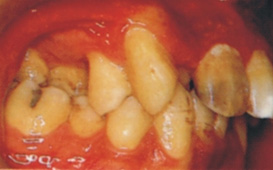

許多人有「牙齒不整齊不是病」的錯誤觀念,同時,認為矯正治療只是個改進美觀的「美容整型治療」 ; 固然齒列矯正治療可以有效的促進臉部的美觀,但齒列不整可同時產生功能與健康的問題,臨床資料明顯顯示,齒顎不整的病者易產生蛀牙及牙周病,但因為這類疾病是個慢性與漸進的,發病初期並無明顯感覺,它因此造成許多人疏於治療,當發病時已相當嚴重。 因此,齒列矯正治療並非只是美容治療,它實質上可同時促進咬合功能與口腔的健康。